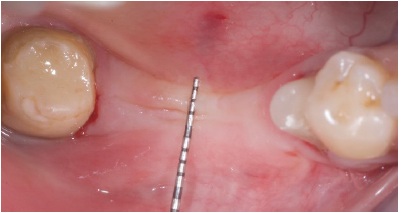

The falps were than advanced to accommodate the new volume and sutured with PTFE 4.0

sutures. 8 Months after surgery one can notice the new aspect of the ridge (Figure 7) and after flaps were opened to exposed the new ridge one can notice that the

new horizontal volume coud than receive 4.2mm diameter implants

Figure 7: Healing at 8 months post op.